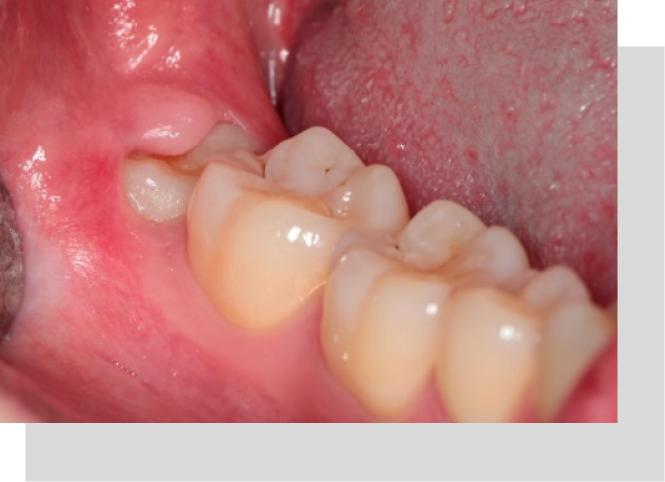

Extracción De Terceros Molares (Muelas Del Juicio):

Consiste en la extracción de las muelas del juicio en casos como:

- Dolor, infección o inflamación repetidas veces en zonas posteriores de los maxilares

- Indicación antes, durante o después del tratamiento de ortodoncia (frenillos)

- Daño a los dientes vecinos por parte de la muela del juicio

- Mala posición de la muela del juicio

- Generación de enfermedad de las encías por parte de la muela del juicio